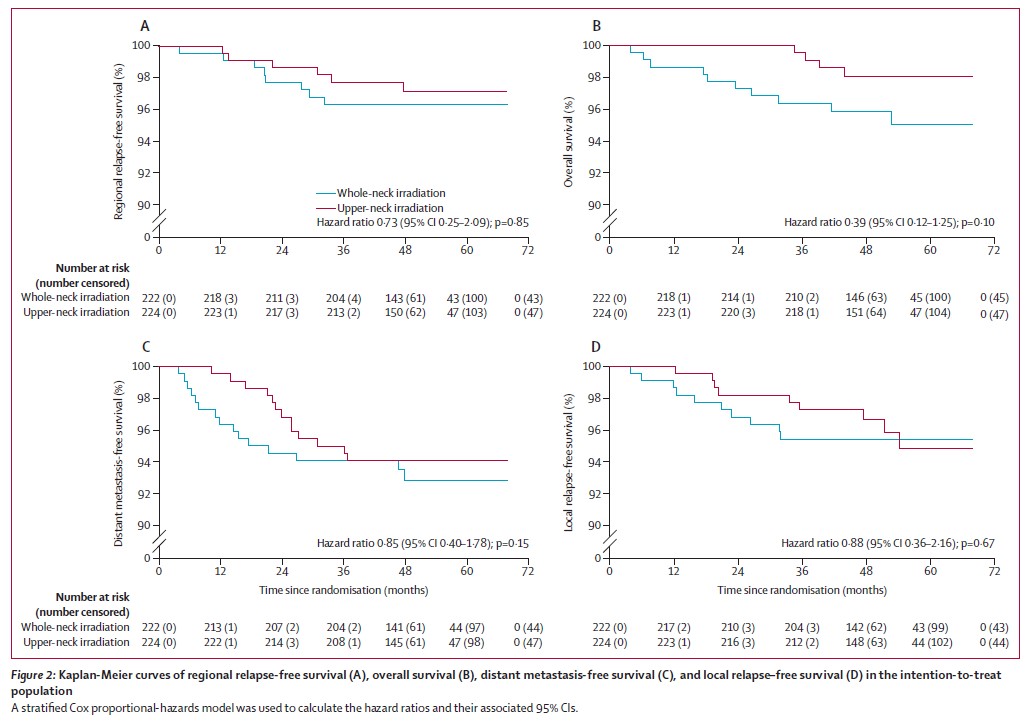

共入组446例患者,中位随访53个月。3年无淋巴结复发生存率在上颈部照射组和全颈部照射组相似(97.7% vs 96.3%,P = 0.85,见下图),非劣效性检验表明上颈部照射组的生存率不差于全颈部照射组。

半颈照射组与全颈照射组生存曲线比较

(两组的颈部复发率、总生存率、远处转移率及局部复发率均无统计学差异)